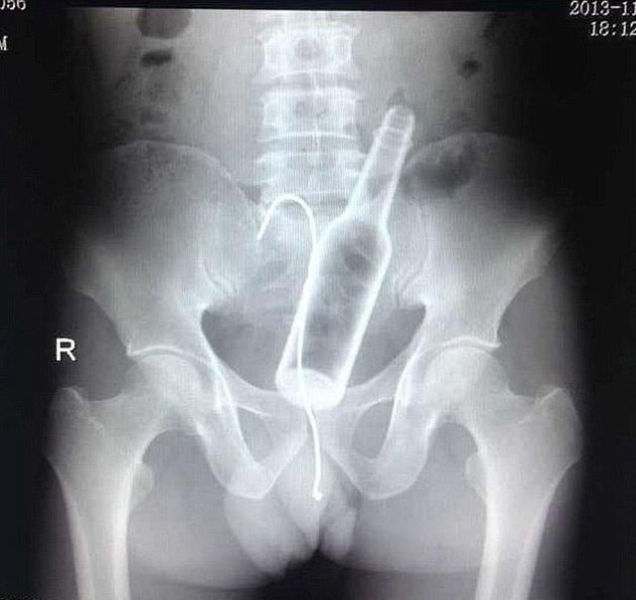

A Chinese man was complaining of stomach pains.The man, was forced to seek medical help after failing to extract a bottle with a curved piece of wire. When medical staff quizzed him on the pain, he claimed he did not know what was causing his discomfort.But he suddenly remembered what had happened when staff presented him with clear X-rays showing the bottle and wire inside of him. He admitted inserting the bottle at home before it became stuck and said he used a steel wire in an attempt to get it back out in a moment of panic.